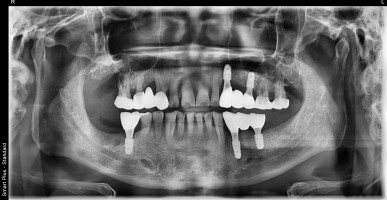

치주염(풍치) 치아 발치 후 임플란트

환자분은 풍치(치주염)으로 인하여 치아 흔들림과 통증으로 내원하셨습니다. 이미 어금니는 심하게 흔들리고 있어 살리지 못한 상태가 되었습니다. 뿌리 끝 부분 넘어서까지 뼈가 녹아 내렸고, 염증도 심한 상태였답니다. 염증이 사라지고 뼈가 차오르기까지 기다린 후 임플란트 . . .